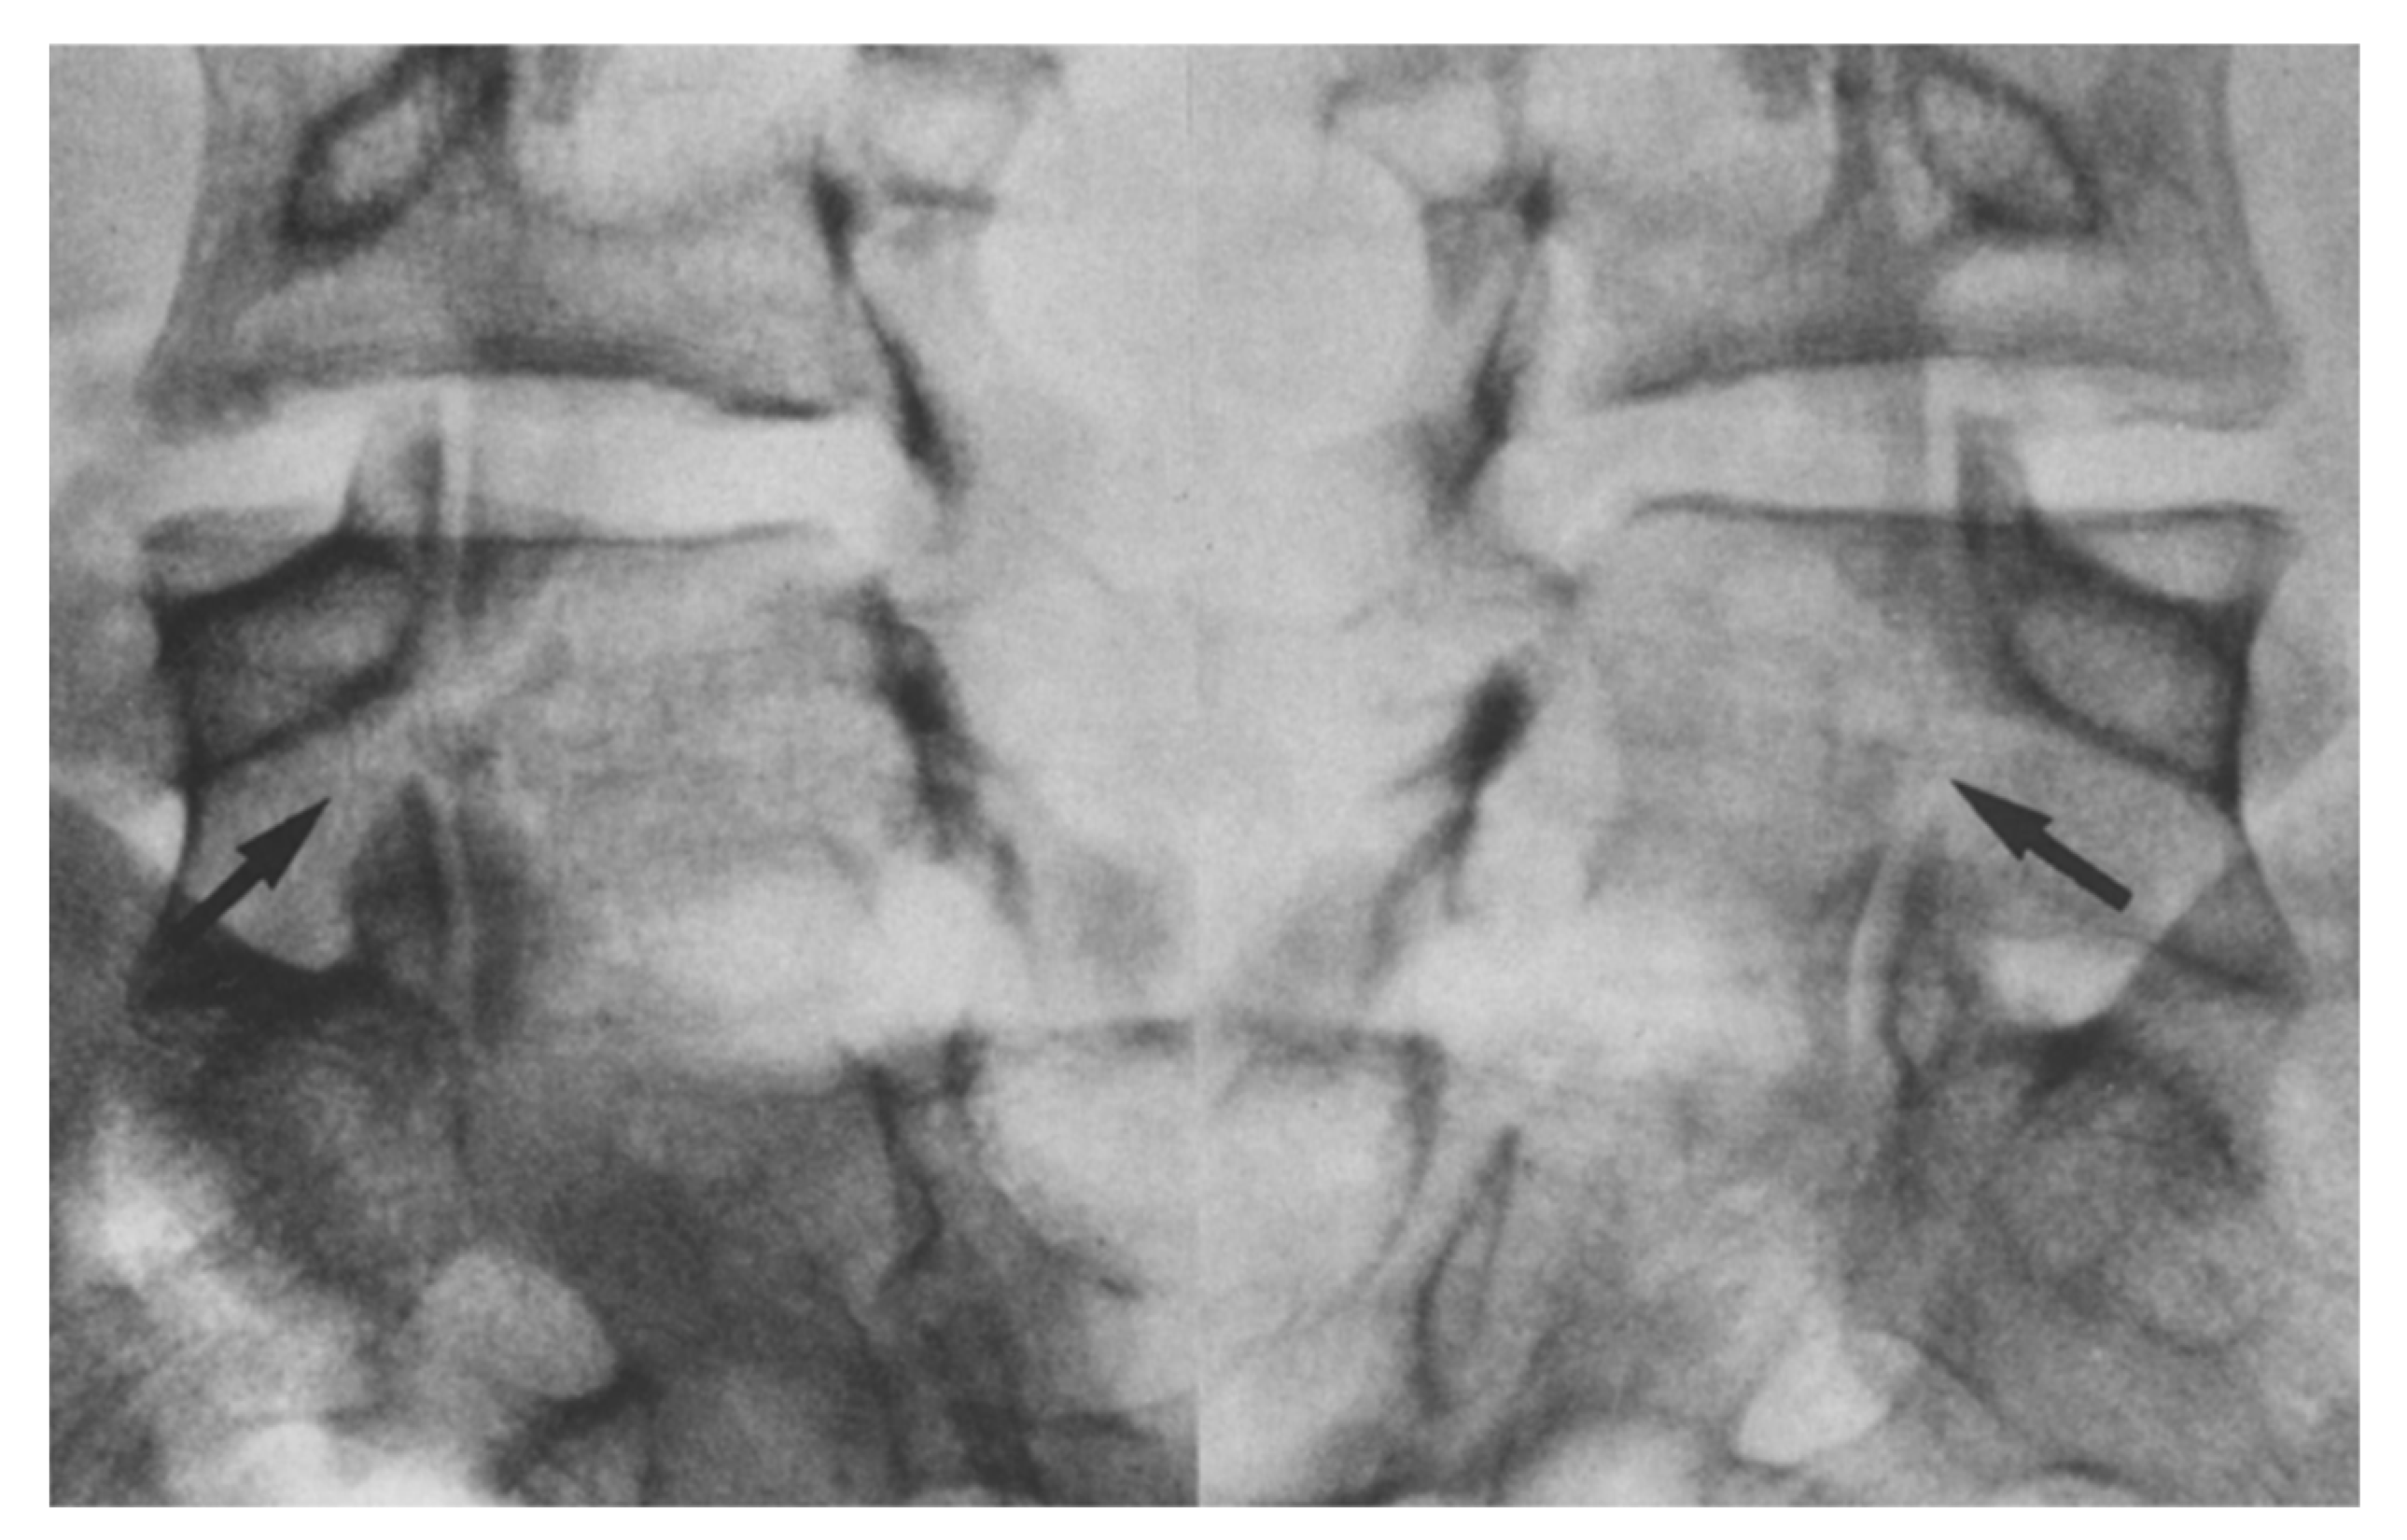

1.9.3. Scott’s Wiring Technique

- Nicol, R.O.; Scott, J.H. Lytic spondylolysis. Repair by wiring. Spine 1986, 11, 1027–1030. [Google Scholar] [CrossRef]

- Johnson, G.V.; Thompson, A.G. The Scott wiring technique for direct repair of lumbar spondylolysis. J. Bone Jt. Surg. Br. Vol. 1992, 74, 426–430. [Google Scholar] [CrossRef]

- Hioki, A.; Miyamoto, K.; Sadamasu, A.; Nozawa, S.; Ogawa, H.; Fushimi, K.; Hosoe, H.; Shimizu, K. Repair of pars defects by segmental transverse wiring for athletes with symptomatic spondylolysis: Relationship between bony union and postoperative symptoms. Spine 2012, 37, 802–807. [Google Scholar] [CrossRef] [PubMed]